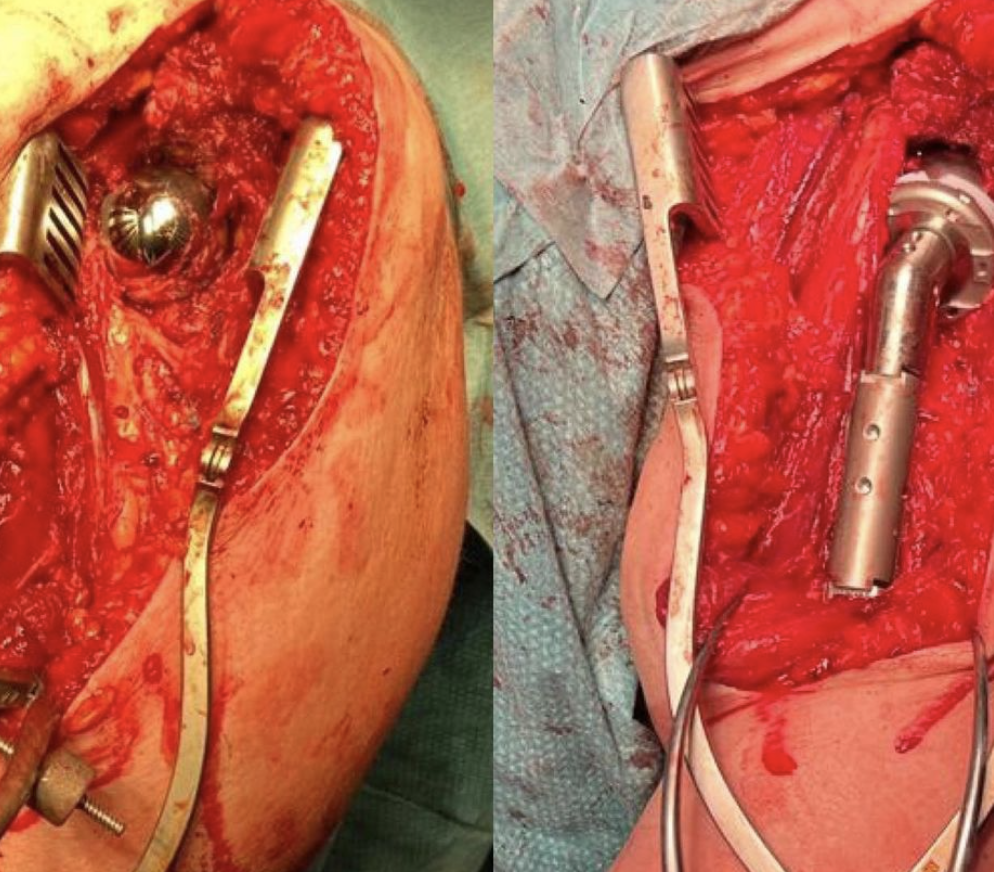

Condrosarcoma intraextrapélvico

Un paciente de 50 años fue intervenido quirúrgicamente hace aproximadamente 1 año para la resección de un Condrosarcoma intraextrapélvico de grado 3 con márgenes libres. Durante la cirugía, se utilizó un espaciador temporal y, posteriormente, se procedió a la fabricación de una prótesis pélvica a medida mediante el enlace proporcionado.

La reconstrucción definitiva se llevó a cabo hace unos 6 meses. A día de hoy, el paciente se encuentra libre de enfermedad y ha logrado una movilidad satisfactoria, caminando con la ayuda de una muleta.

Paciente de 50 años intervenido hace 1 año realizando resección de Condrosarcoma intra extrapelvico grado 3 con márgenes libres y reconstruyendo con espaciador temporal.

Se fabrica prótesis pélvica a medida Link, realizándose la reconstrucción definitiva hace 6 meses.

Actualmente libre de enfermedad y caminando con una muleta.